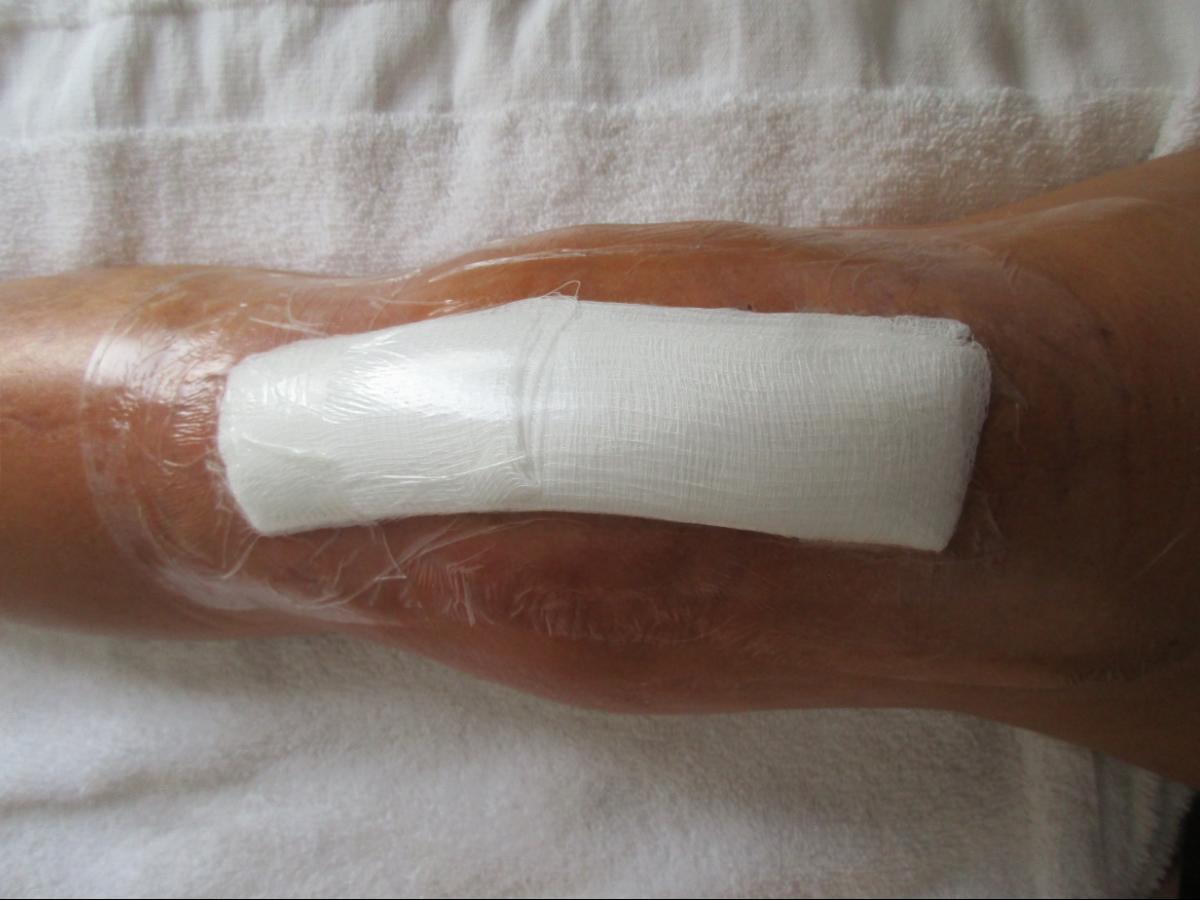

25AUG19 day before surgery, shin has healed and cleared for pool...

...will be a while before able to get into the pool again... (click to enlarge):